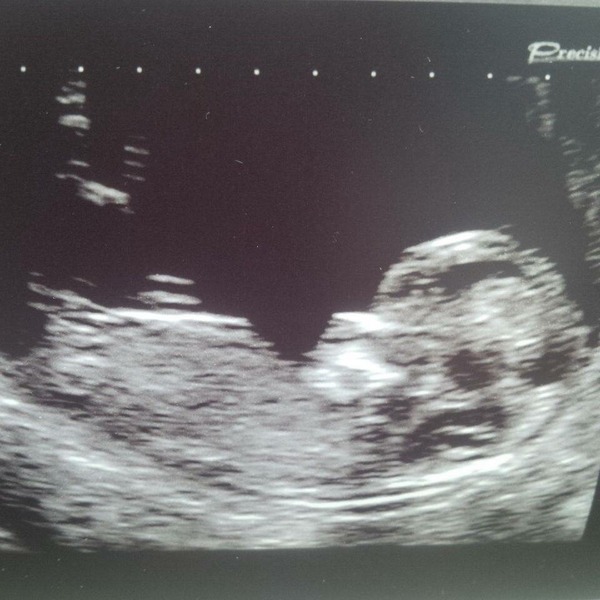

We would have done the Harmony, as I'm 38 and I've read that it is so much more accurate than the NHS tests, but money is very tight just now as DH is in between jobs. We paid for a private Nuchal scan so that we could tell our families over the holidays, but couldn't stretch to the Harmony. Perhaps if I am lucky enough to get pregnant again it will be available on the NHS by then!

12 weeks today